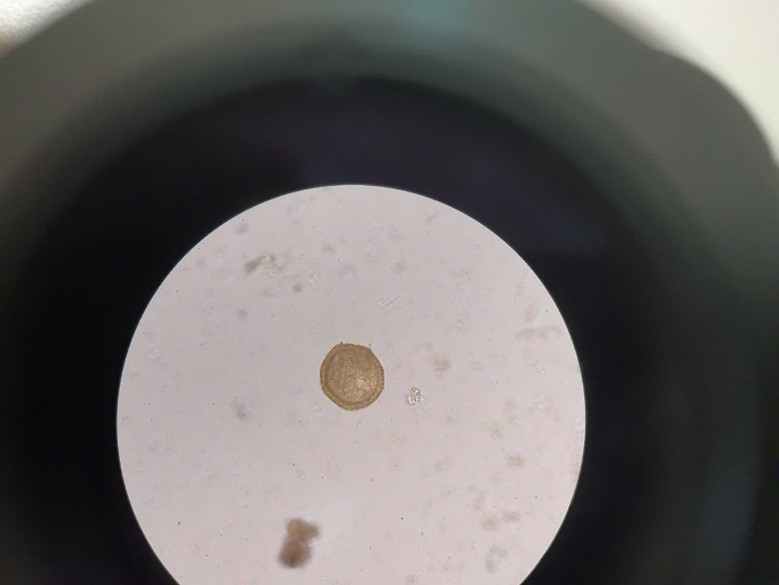

Hình ảnh trứng giun móc dưới kính hiển vi